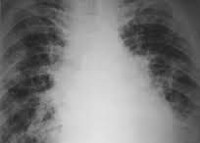

J67.9 Гиперсенситивный пневмонит, вызванный неуточненной органической пылью